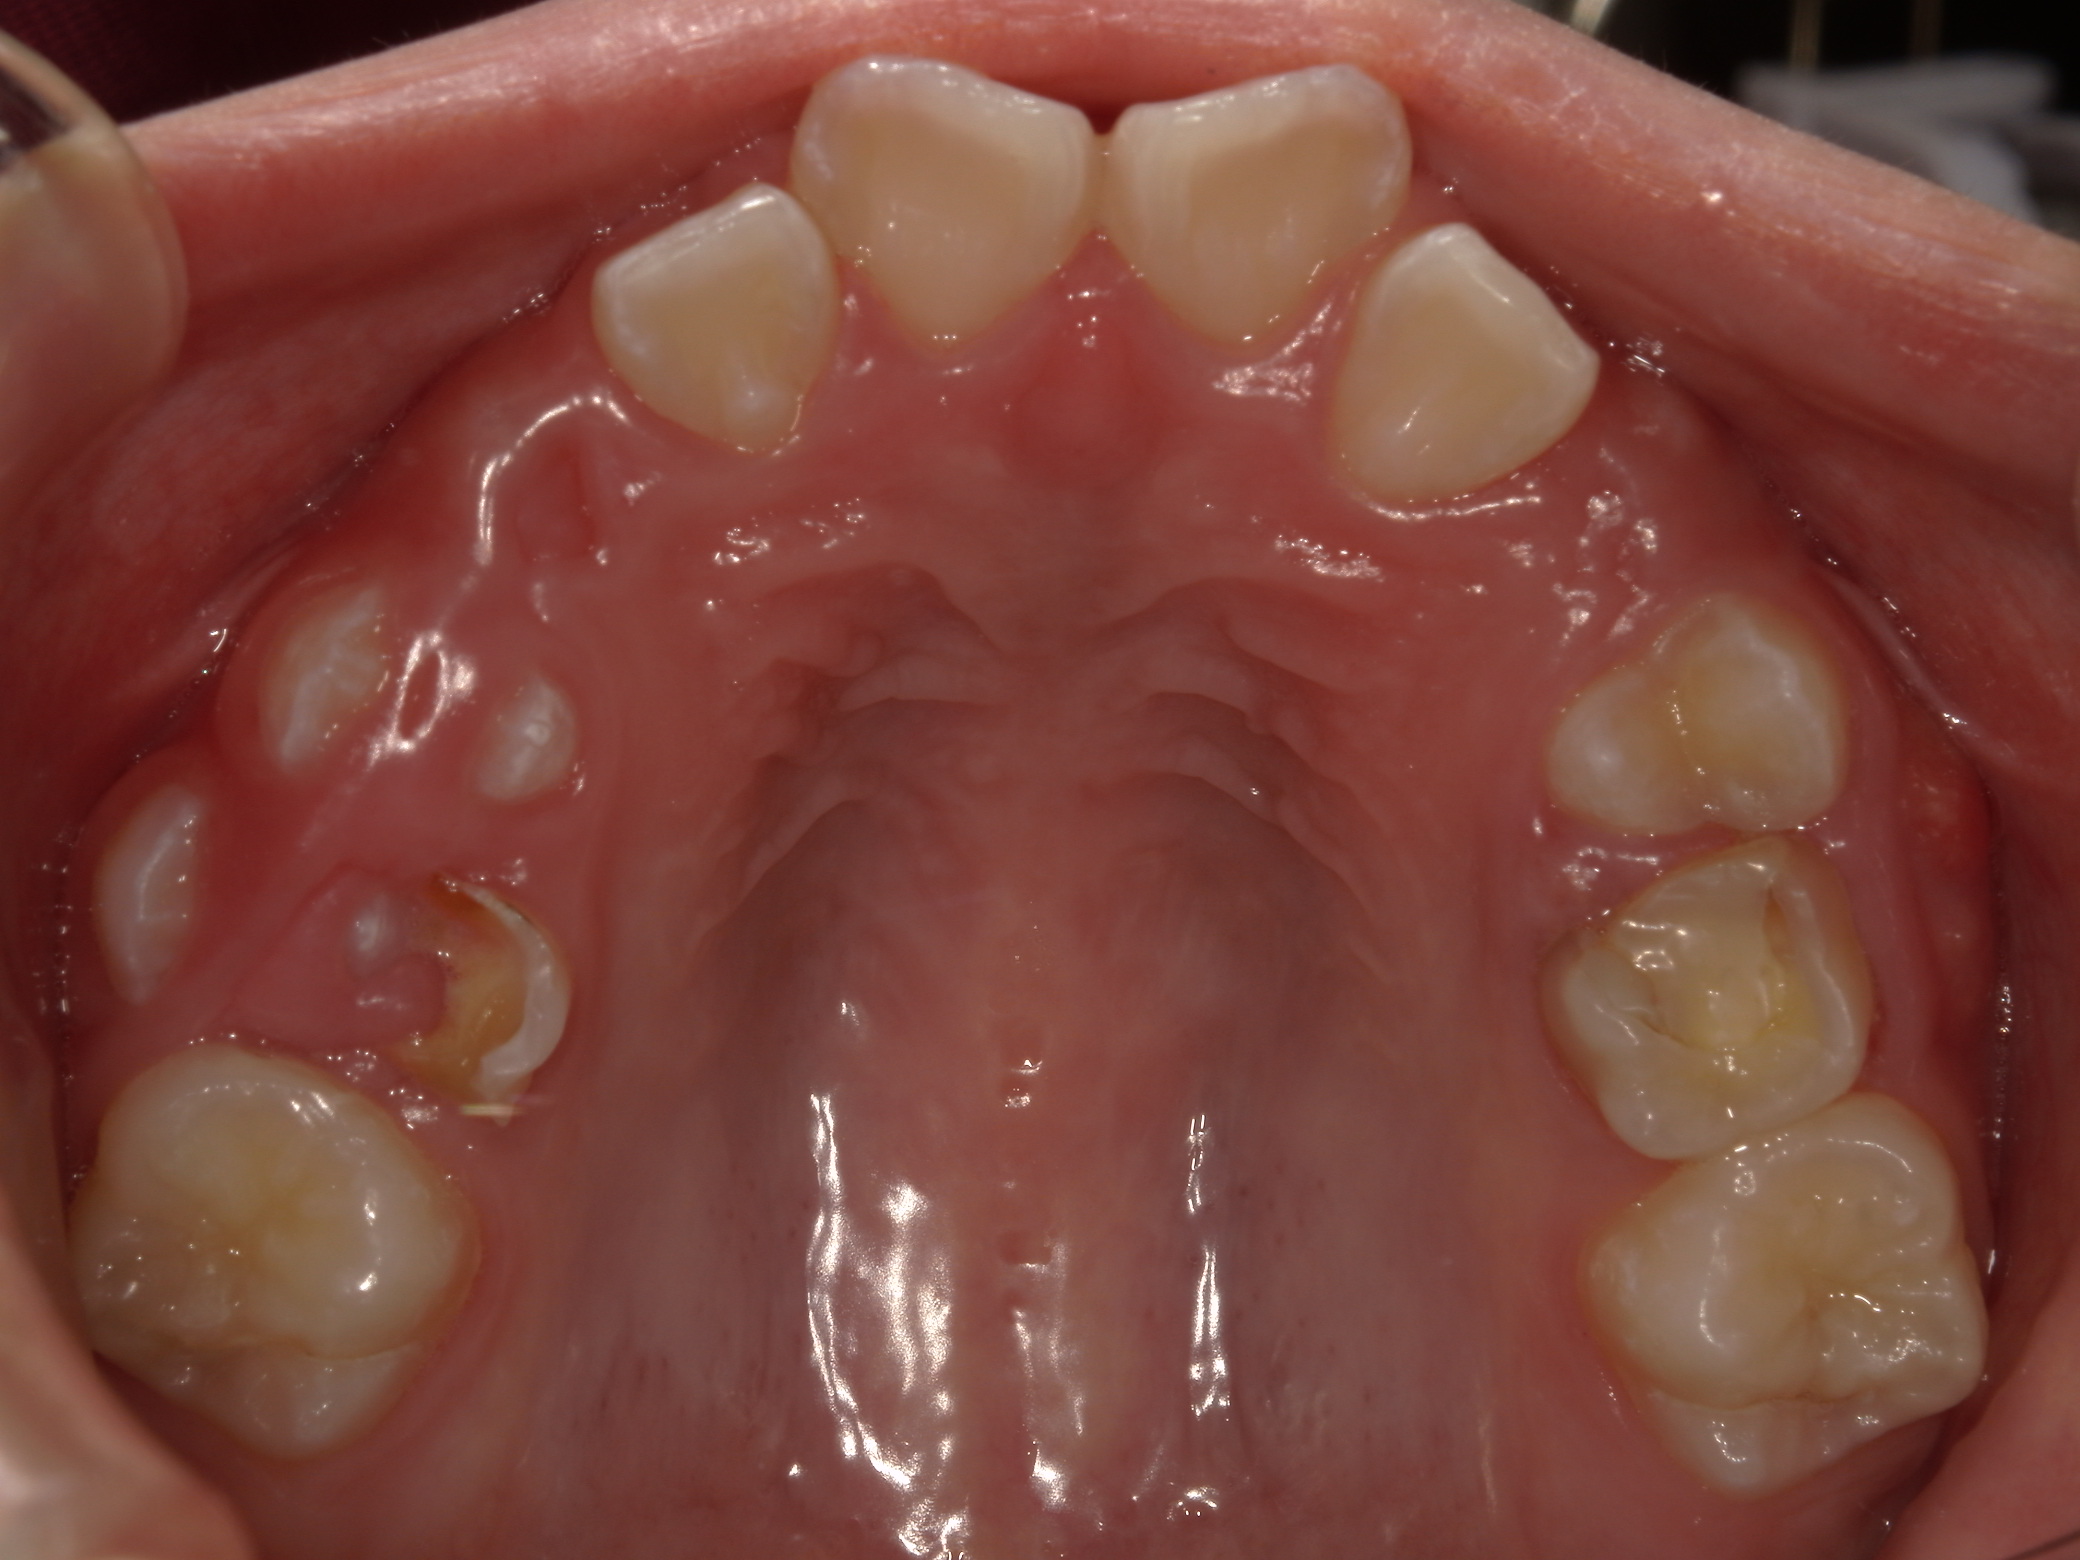

| 年齢・性別 | 7歳1ヶ月の男児 |

|---|---|

| 主訴 | 歯の生えるスペース不足が懸念され、歯列の乱れ(叢生)を整えるために来院された患者様です。 |

| 治療期間・回数 | 1年3ヶ月・11回 |

| 費用 | 420,000円(税別) |